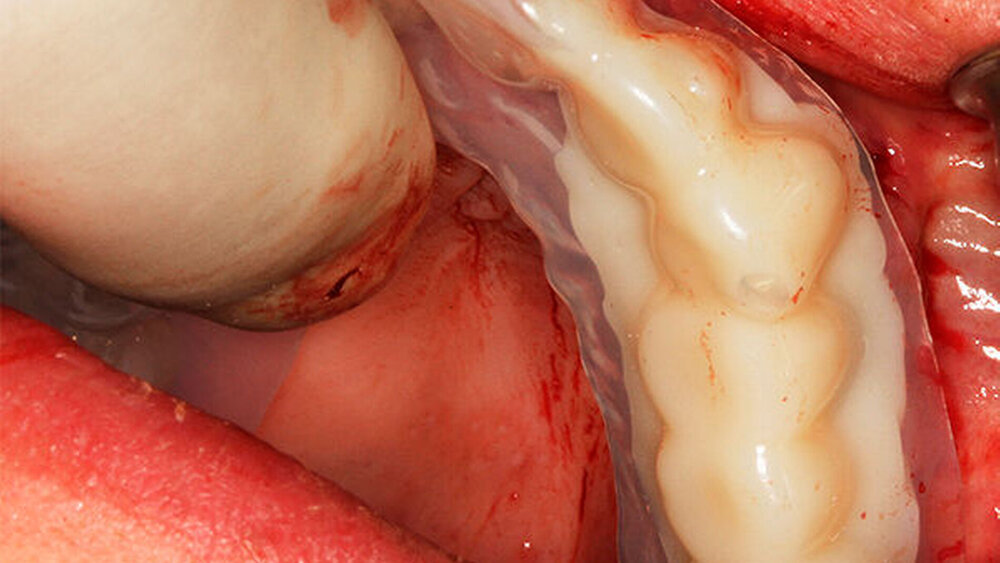

Ich auch, entsprechend konservativ sieht unser Konzept aus, nach dem ich auch meine Frau behandeln würde. Ich ziehe den nicht erhaltungswürdigen Zahn, lege Kollagen ein, kein KEM, um das Blutkoagulum zu stützen. Nach sechs Wochen setze ich entsprechend den prothetischen Rahmenbedingungen im Frontzahnbereich das Implantat und nach zwölf Wochen im Seitenzahnbereich. Die bukkale Lamelle stabilisiere ich mit einem resorptionsstabilen KEM. Dann erfolgt die Abdeckung mit einer Membran (GBR). Für dieses Vorgehen gibt es sehr schöne Zehnjahresergebnisse von Chappuis et al. aus der Berner Arbeitsgruppe, die letztes Jahr veröffentlicht wurden. Für diese Indikation würde ich auch ein BLX verwenden.